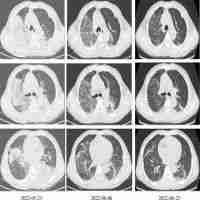

| Abstract | Background Chlamydia psittaci (C. psittaci) causes parrot fever in humans. Development of metagenomic next-generation sequencing (mNGS) enables the identification of C. psittaci. Methods This study aimed to determine the epidemiological and clinical characteristics of parrot fever cases in China. A multi-center observational study was conducted in 44 tertiary and secondary hospitals across 14 provinces and municipalities between April 2019 and October 2021. Results A total of 4545 patients with complicated or atypical pulmonary infection were included in the study, among which the prevalence of C. psittaci was determined to be 2.1% using mNGS. The prevalence of C. psittaci was further determined across demographic groups and types of specimens. It was significantly higher in patients with senior age (2.6% in those > 50 years), winter-spring (3.6%; particularly in December, January, and February), and southwestern (3.4%) and central and southern China (2.7%) (each P < 0.001). Moreover, the prevalence was the highest in bronchoalveolar lavage fluid (BALF) (2.9%), compared with sputum (1.1%) and peripheral blood specimens (0.9%). Additionally, co-infection of principal microorganisms was compared. Certain microorganisms were more likely to co-infect in parrot fever cases, such as Candida albicans in BALF (26.7%) and peripheral blood (6.3%), compared with non-parrot fever cases (19.7% and 1.3%); however, they did not significantly differ (each P > 0.05). Conclusion Parrot fever remains low in patients with complicated or atypical pulmonary infection. It is likely to occur in winter-spring and southwestern region in China. BALF may be the optimal specimen in the application of mNGS. Co-infection of multiple microorganisms should be further considered. |